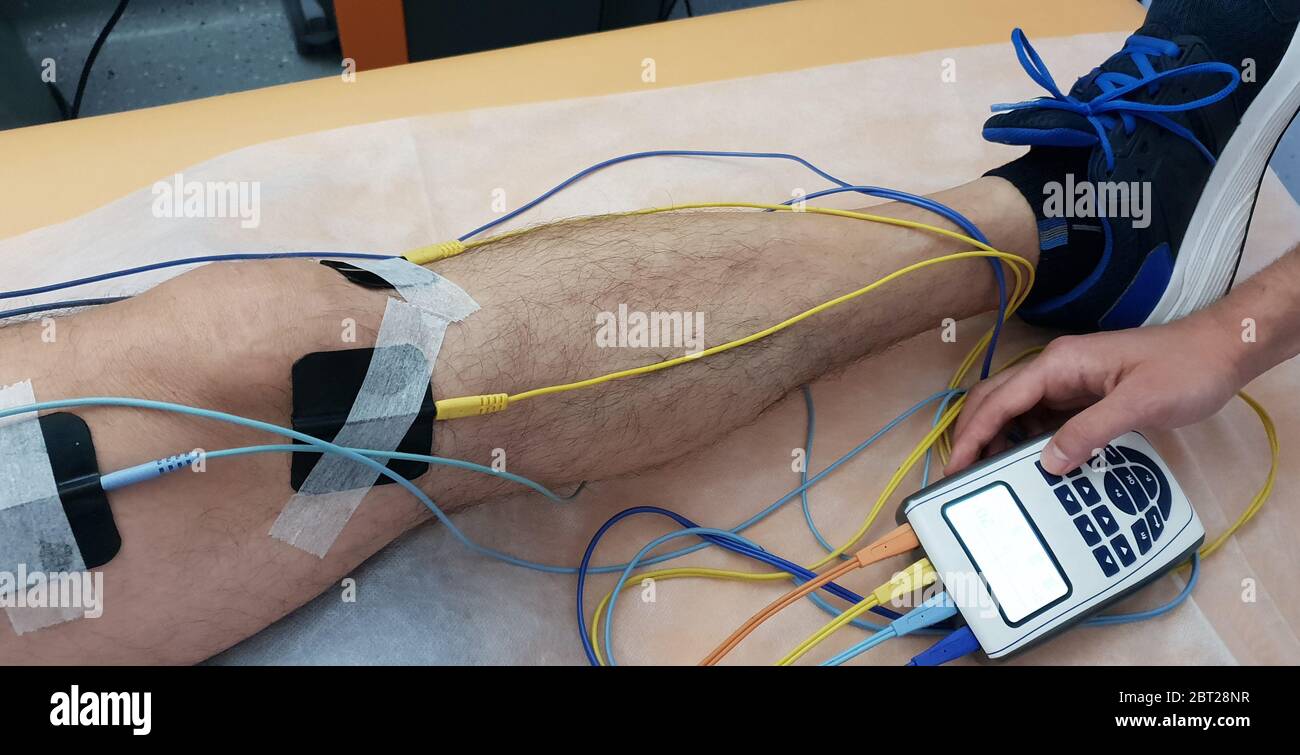

Électrostimulation des quadriceps comme thérapie de physiothérapie Banque D'Imageshttps://www.alamyimages.fr/image-license-details/?v=1https://www.alamyimages.fr/electrostimulation-des-quadriceps-comme-therapie-de-physiotherapie-image359009891.html

Électrostimulation des quadriceps comme thérapie de physiothérapie Banque D'Imageshttps://www.alamyimages.fr/image-license-details/?v=1https://www.alamyimages.fr/electrostimulation-des-quadriceps-comme-therapie-de-physiotherapie-image359009891.htmlRF2BT28NR–Électrostimulation des quadriceps comme thérapie de physiothérapie